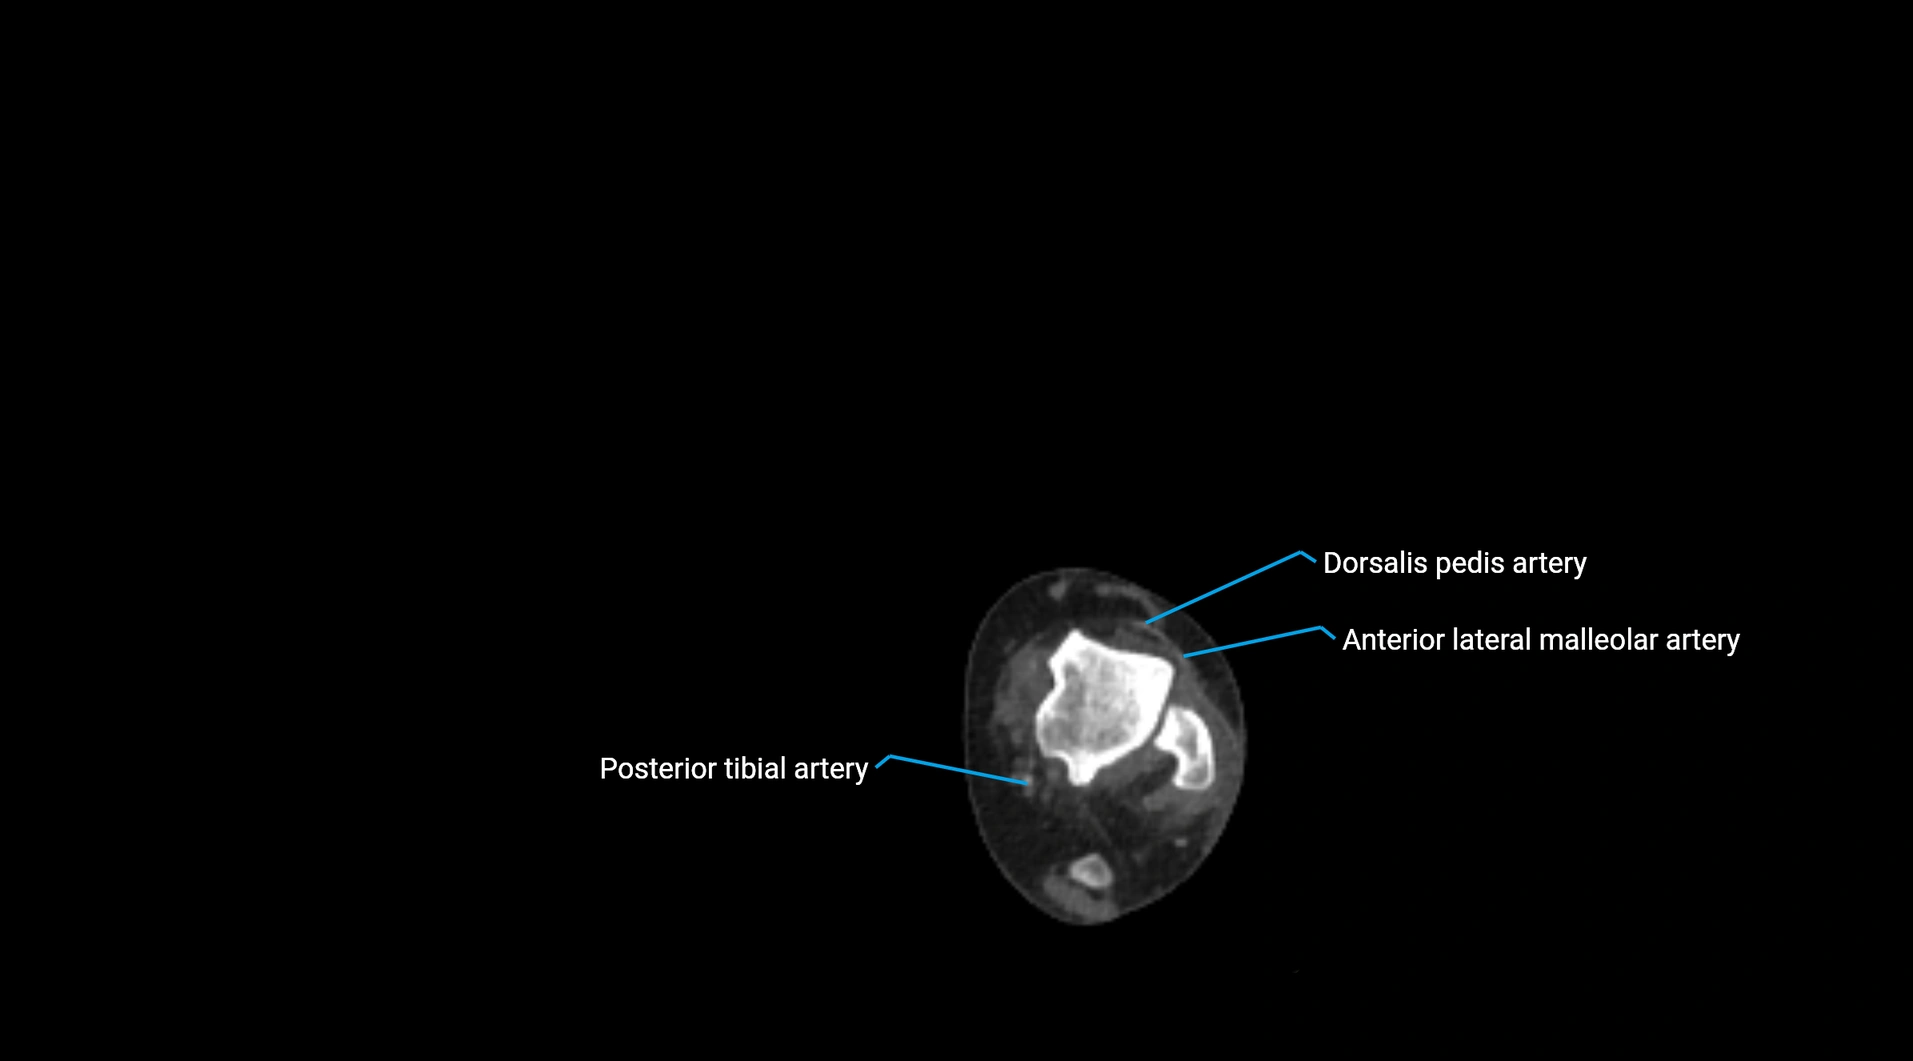

CT images

image